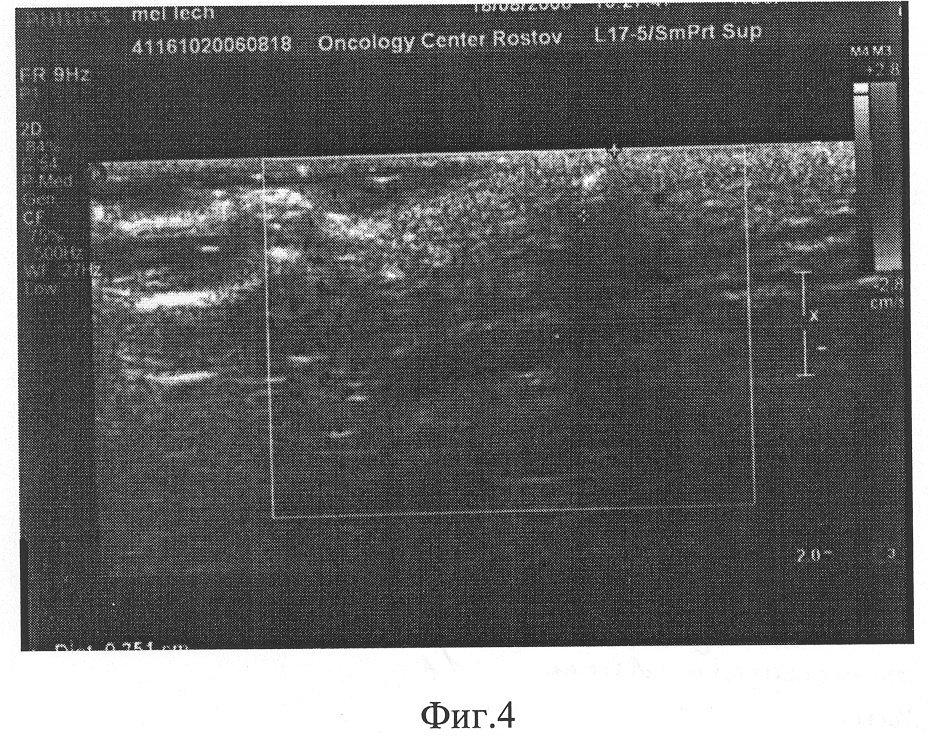

Далее была проведена трехмерная ангиография для уточнения васкуляризации образования. В результате проведенного исследования было установлено, что образование имеет сосудистую ножку в основании, которая частично распространяется в подкожную клетчатку (Фиг.1). После произвели на коже маркировку точек предполагаемых проколов для введения химиопрепаратов вне сосудистого русла (Фиг.2).

Комплексное лечение заключалось в следующем: 20.08.2004 г. провели паратуморальную аутоплазмохимиотерапию: пунктировали локтевую вену, забрали 20 мл крови, центрифугировали ее в течение 30 мин при 1500 об/мин. Затем плазму крови инкубировали с цитостатиками: цисплатин – 10 мг, метотрексат – 25 мг, циклофосфана – 600 мг в термостате в течение 30 мин, при температуре 37°С, а затем ввели пациенту в подкожную жировую клетчатку непосредственно под очаг злокачественного роста, через намеченные под контролем УЗИ точки вне сосудистого русла, отступая 1,5 см от края опухоли проколами под углом 45° (Фиг.3, 4). В этот же день начали сеансы дистанционной гамма-терапии в очаговой дозе 2,4 Гр в течение 15 дней. Суммарная очаговая доза дистанционной гамма-терапии – 36 Гр. После окончания первого этапа лечения визуально уменьшился экзофитный компонент образования, появились очаги депигментации. При повторном УЗ-исследовании отмечена положительная динамика. 5.09.2004 г. больной был переведен в отд. реконструктивно-пластической хирургии, где ему была выполнена операция – широкое иссечение меланомы кожи спины с пластикой серповидным кожным лоскутом. Послеоперационный период протекал гладко, без особенностей. Швы сняты на 13-е сутки. Гистологический анализ от 5.09.2004 г. №733322-324 – меланома из эпителиоподобных и невусоподобных клеток с умеренным содержанием меланина, очагами изъязвления, фиброза. Инвазия III-IV уровня по Кларку. Толщина опухоли по Бреслоу – 4,5 мм, выраженная лимфоцитарная инфильтрация с наличием большого количества гигантских многоядерных клеток, типа инородных тел. Больной находится под наблюдением в течение двух лет без признаков рецидива.